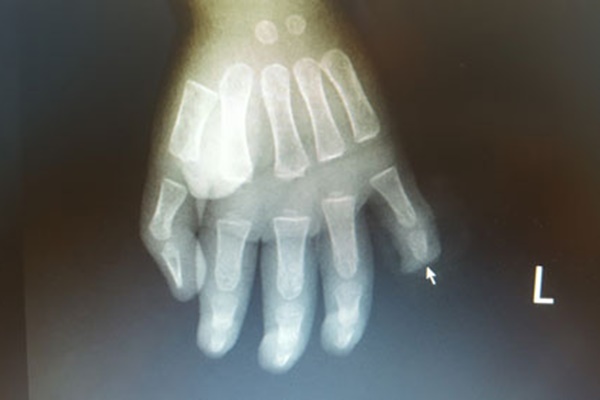

Hình ảnh phim chụp X.Quang bàn tay trái của bệnh nhi

Trẻ nhập viện ngày 19/5/2020 với vết thương đứt rời đốt 3 ngón 5 bàn tay trái, chảy rất nhiều máu. Các bác sĩ Khoa Chấn thương - Chỉnh hình & Bỏng đã tiến hành phẫu thuật tạo mỏm cụt ngón và đốt ngón tay số 5 cho trẻ. Hiện sức khỏe của bé hiện nay đã ổn định.